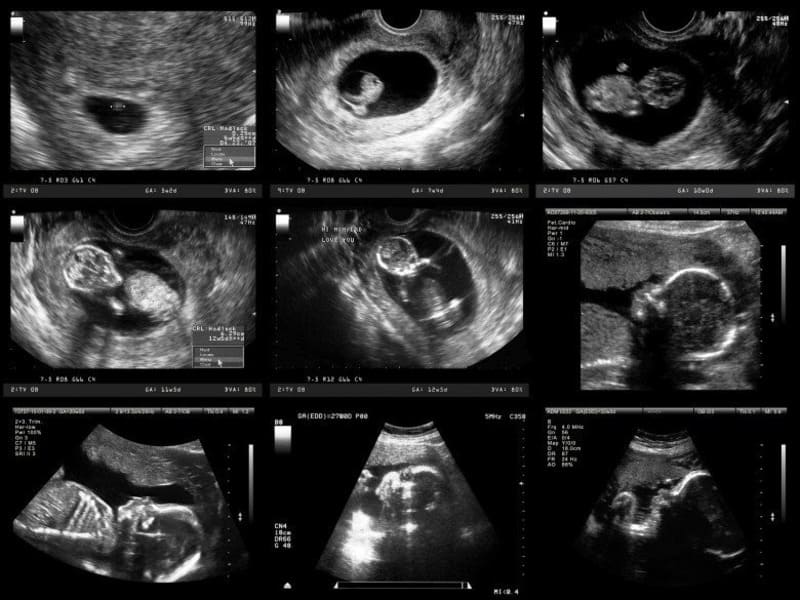

Chỉ số siêu âm thai theo tuần là căn cứ quan trọng giúp theo dõi sự phát triển của thai nhi trong từng giai đoạn. Việc nắm rõ các chỉ số chuẩn giúp mẹ bầu chủ động chăm sóc sức khỏe và phát hiện sớm những bất thường. Cùng Mẹ Bầu Xứ Nghệ tìm hiểu chi tiết bảng chỉ số siêu âm thai theo tuần trong bài viết dưới đây.

Theo dõi chỉ số siêu âm thai theo tuần giúp bác sĩ đánh giá sự phát triển của thai nhi, phát hiện sớm các bất thường và theo dõi sức khỏe mẹ bầu. Mỗi giai đoạn thai kỳ sẽ có những chỉ số quan trọng như chiều dài, cân nặng thai, lượng nước ối, và nhịp tim thai. Việc siêu âm đúng lịch giúp mẹ bầu nắm rõ tình hình phát triển của bé và có hướng chăm sóc kịp thời.

Các chỉ số siêu âm thai theo tuần cần quan tâm giúp bác sĩ và mẹ bầu theo dõi sự phát triển của bé một cách chính xác và toàn diện. Mỗi giai đoạn thai kỳ, các chỉ số như CRL, BPD, HC, AC, FL hay EFW đều được đo lường và so sánh với chuẩn để đánh giá sức khỏe thai nhi. Dưới đây là những chỉ số quan trọng cần theo dõi theo từng tuần: